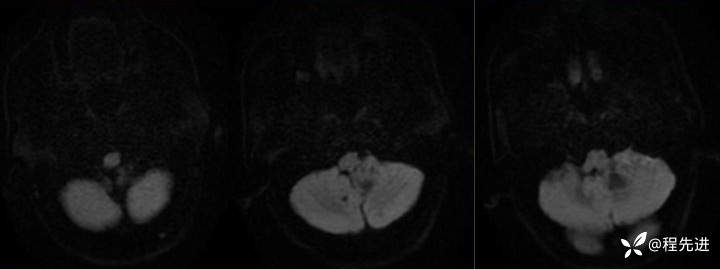

CT:

img